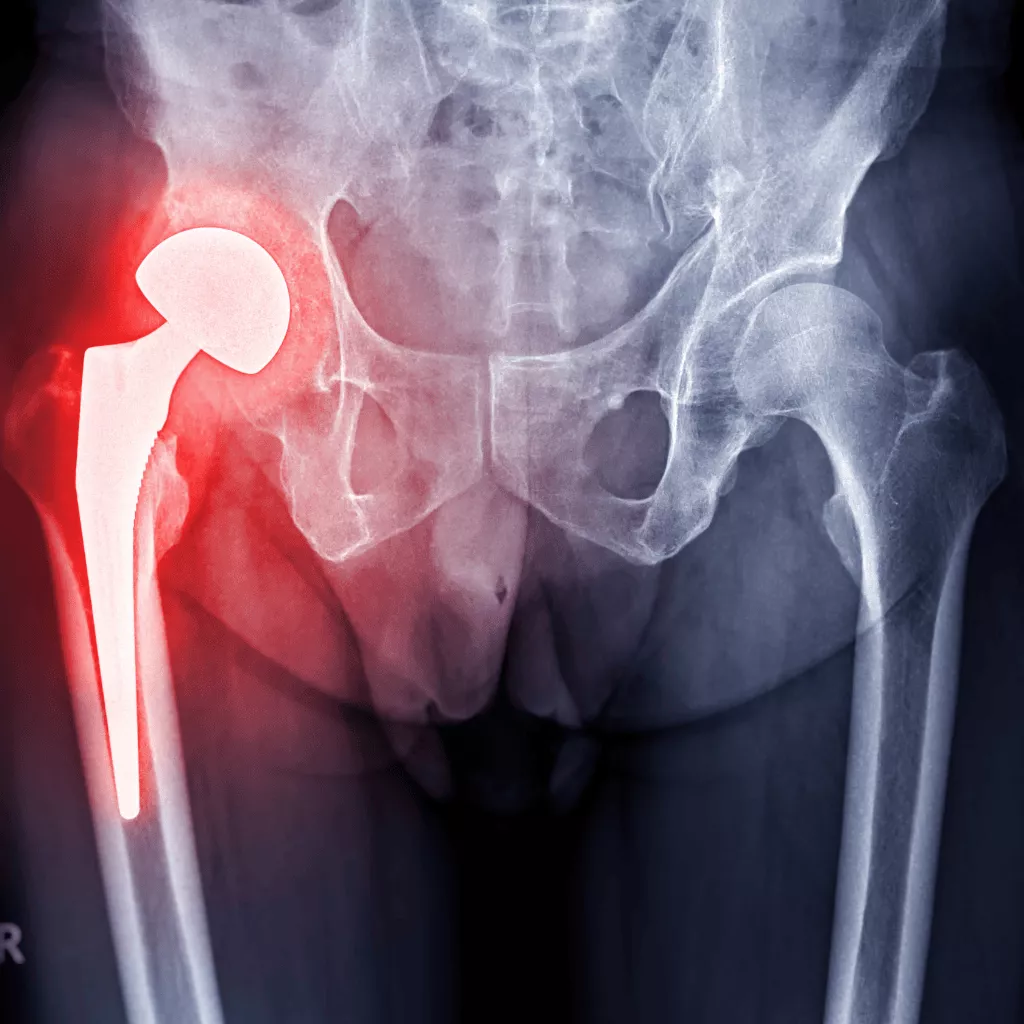

The processed material is then injected into the joint or tissue needing repair. It acts as a biological cushion, supporting healing and reducing inflammation over time.

Veterans may benefit from injections into the knee, hip, ankle, or shoulder, all areas where degenerative pain can severely affect quality of life. Unlike other options, Adipose-derived stem cells (ADSC's) Therapy uses no synthetic chemicals, no expanded cells, and no foreign substances, just your body, helping itself.